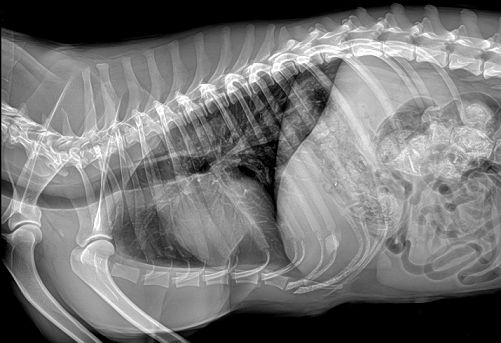

国产品牌普爱医疗宠物DRhttp ://ww w. pl 999. co m/class .php? anclss =1&nclass =412采用非晶硅平板探测器,可以令动物影像成像清晰而快速,基本上5s左右就能使动物影像清楚成像且无拖尾现象,而且分辨率高,极限空间分辨率可达到5.0Lp/mm;

普爱医疗宠物DR拍摄的高清照片

同时,宠物影像成像尺寸较大,成像尺寸可达43cm x 43cm,并且以DICOM格式储存数据,极大的方便了医疗工作者们追踪检查时使用。同时还支持窗宽、窗位、放大、旋转、正像和负像转换等显示功能。想了解产品具体信息,欢迎留言或致电400-6656-888